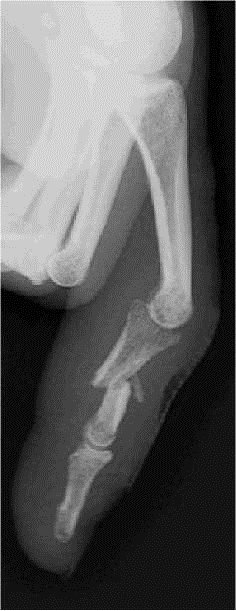

PROFIL

– – Voir les 3 phalanges

IMAGE NORMALE

FRACTURE D’UNE PHALANGE